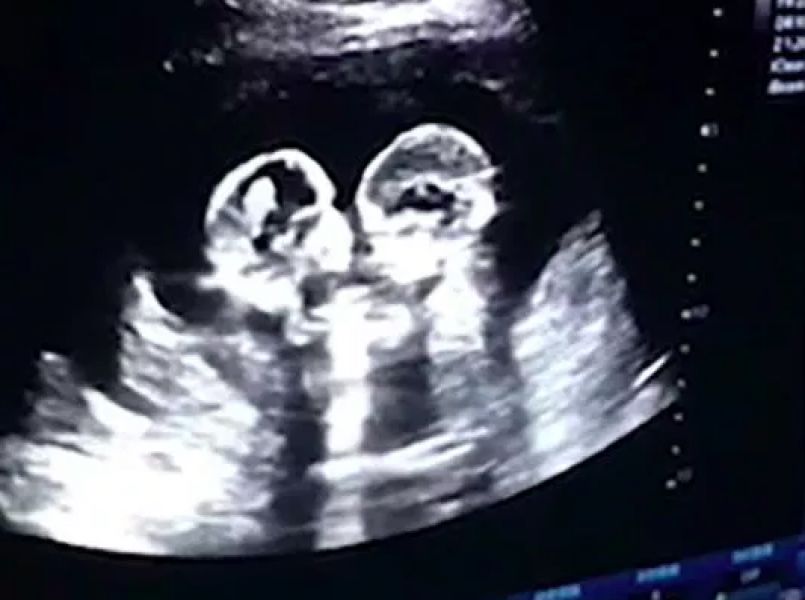

Het is al zo krap in de buik van de moeder, dus als je met z’n tweetjes erin zit, is het soms vechten om iets meer ‘space’. Zo’n gevecht was onlangs tijdens het maken van een echo live te zien: een tweeling bokst met elkaar in de buik van de moeder.

De echo werd gemaakt in China bij een vrouw die vier maanden zwanger is van een tweeling, meldt de Britse versie van Metro. De tweeling deelt een placenta en blijkbaar hadden ze even genoeg van elkaar. Want als je goed kijkt zie je dat de een de ander een hoek geeft en de ander doet dat weer terug.

De vader die het echofilmpje met zijn mobiel filmde, vertelde tegen een Chinese nieuwssite dat hij niet had gedacht dat zijn dochters al voordat ze zijn geboren in het nieuws zouden komen. Ook voegde hij eraan toe dat de twee ook met elkaar knuffelden tijdens het maken van een andere echo. Dus het is gelukkig niet alleen maar haat en nijd, maar een gezonde zussenrelatie;-)